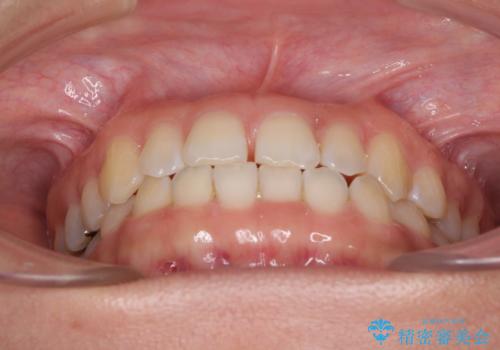

下の前歯が上の前歯を突き上げるように咬合するため、咬み合わせの位置を改善しながら隙間を閉じていきました。

元々の歯並びが悪くなかったため、9ヶ月で綺麗に仕上がりました。

すきっ歯は後戻りを起こしやすいため、上下ともに歯の裏側を細いワイヤーで固定した上で、リテーナーのマウスピースを装着していただいています。